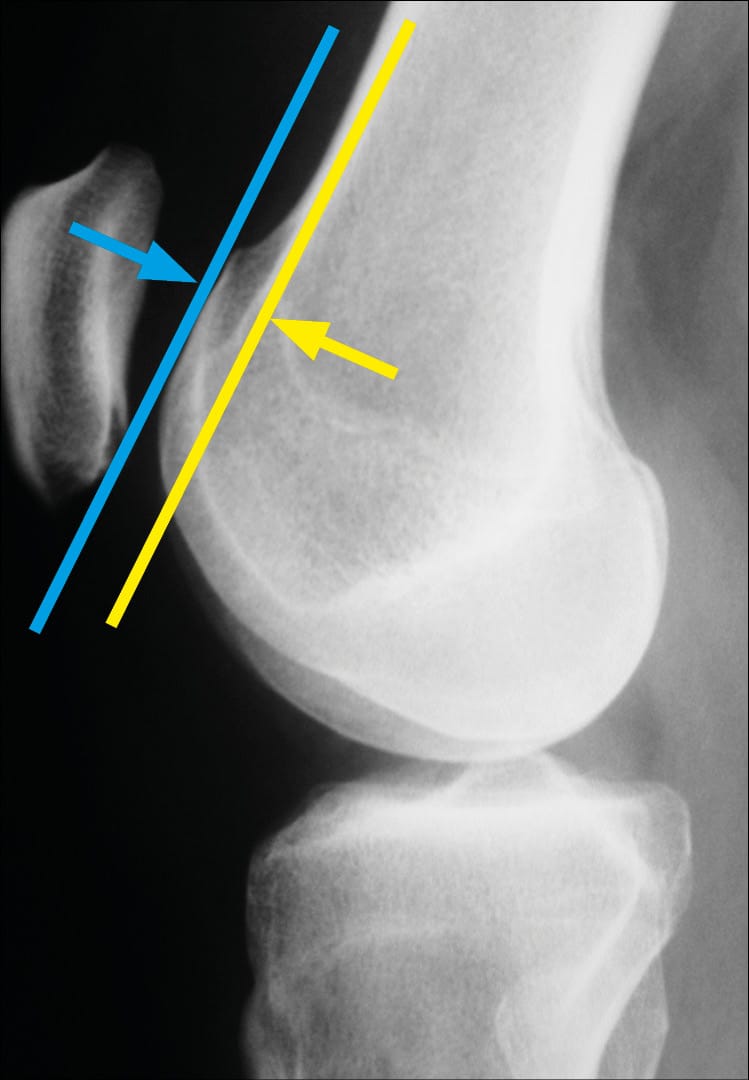

The spur or prominence (Figure 18) is the second essential sign of trochlear dysplasia after the crossing sign. To demonstrate it, a tangent to the anterior cortex is drawn. This line can pass anterior to, at the level of, or posterior to the most anterior point of the trochlear groove line. One can therefore have a negative, zero, or even positive prominence value when this tangent passes posterior to the most anterior point of the trochlear groove.

The mean prominence value was -0.8 mm in a control group, while the mean was 3.2 mm in the group of patients who had experienced one or more patellar dislocations. More importantly, a threshold value of 3 mm could be defined (Figure 19).

Trochlear depth is less well known (Figure 21). It is the third factor that we must analyse on a lateral radiograph. It gives us valuable information about the congruence of the trochlea at 15° of flexion. It represents the distance between the trochlear groove line and the lateral facet. It allows us to know if the trochlea deepens distally. Comparing a group of patients who had experienced one or more patellar dislocations and a control group, a threshold value of 4mm was determined.

The depth, measured at 15°, is not deep enough, not congruent enough, if the depth is less than 4mm. This factor, less essential diagnostically, is crucial prognostically and guides our therapeutic choices. If the trochlea is well-grooved at 15° of flexion, then bringing the patella to face this congruent trochlea, for example by distalisation of the ATT, often ensures good patellar stability.